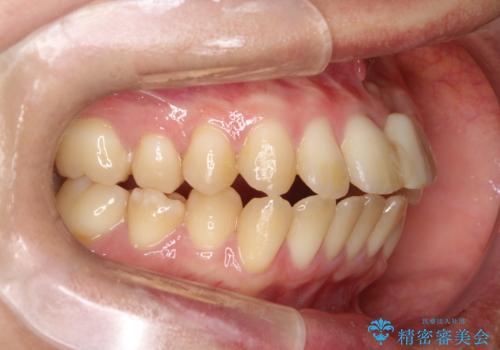

前歯の開咬とシザーズバイトを改善|インビザライン矯正

- 治療計画

前歯が噛まないため咀嚼が困難で、シザーズバイトにより噛み合わせに不調を感じていました。インビザラインを用いて、透明なマウスピースによる目立ちにくい矯正治療を実施。奥歯のシザーズバイトを改善した後、前歯の歯列を緻密に調整し、噛み合わせを整えました。定期的なマウスピース交換を通じて徐々に歯列が改善され、治療終了後には前歯が正常に咬合するようになり、噛み合わせの機能性と審美性が共に向上しました。